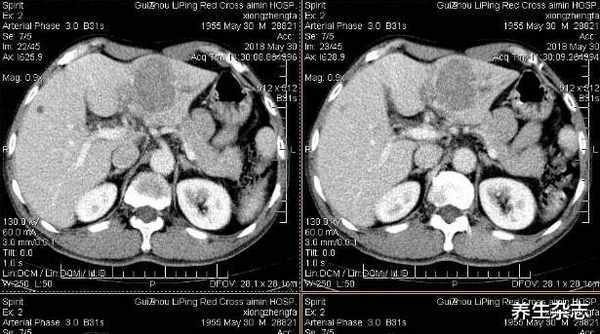

送到医院后,医生经过多项检查,刘大爷甲胎蛋白严重超标,确诊为肝癌,得知检查结果的刘大爷一时间不知所措。